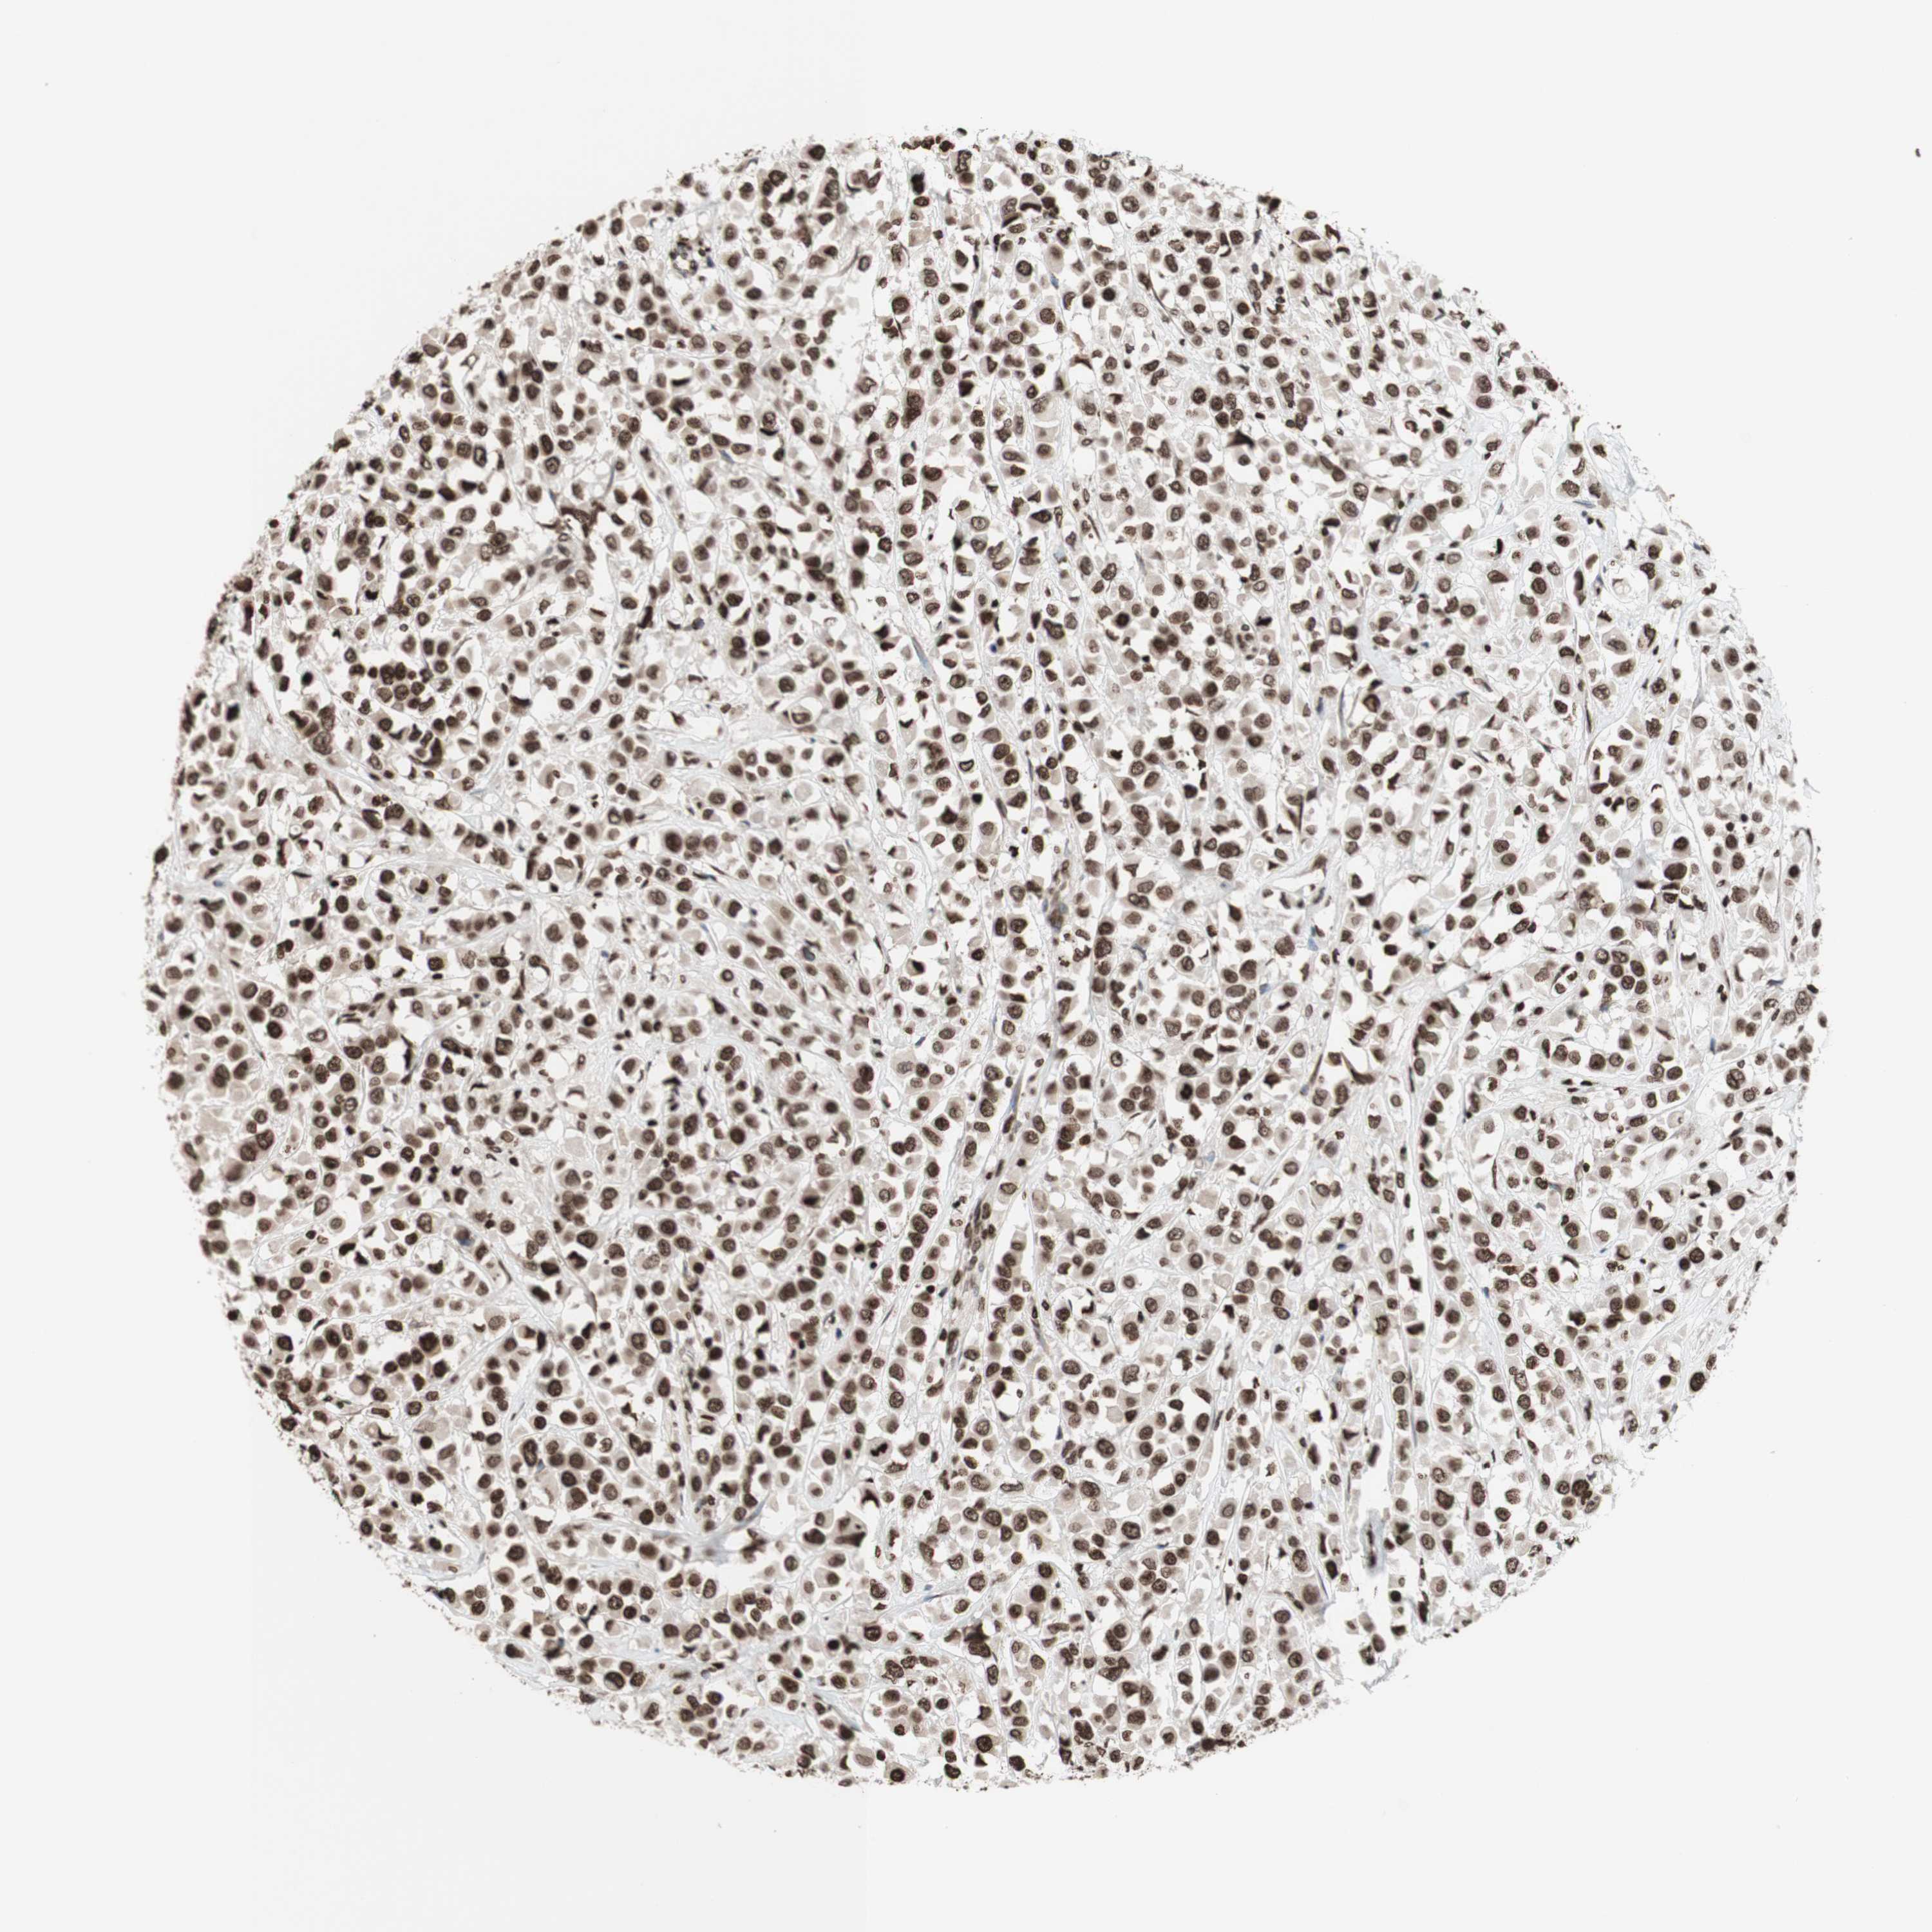

BRCA TCGA BRCA VALIDATION PROTEIN EXPRESSION